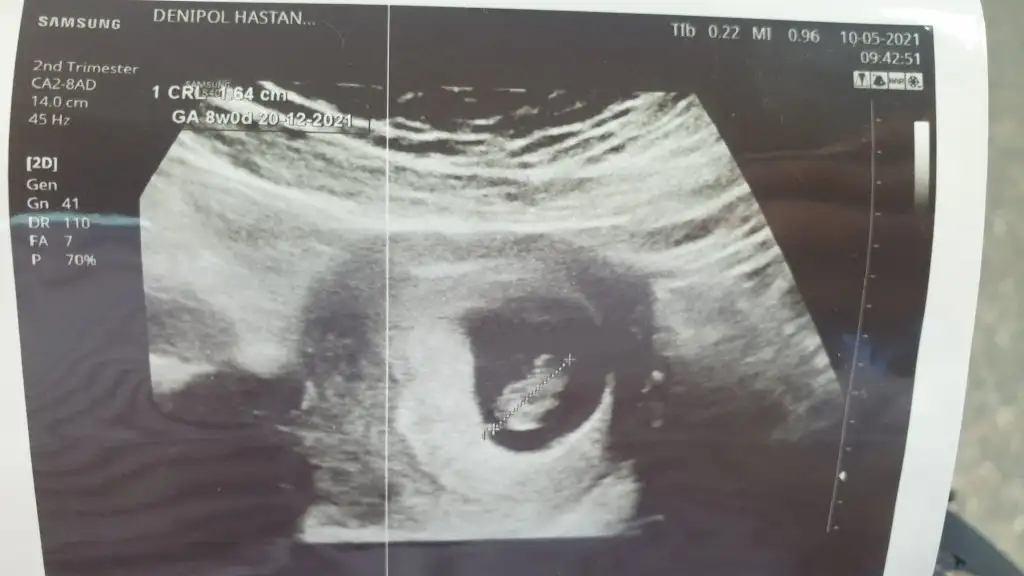

Bana da bakar misiniz ilki 6+4 vajinal diger ikisi 12+5 karindan cinsiyet belli degil henuz tahmin ederseniz sevinirim